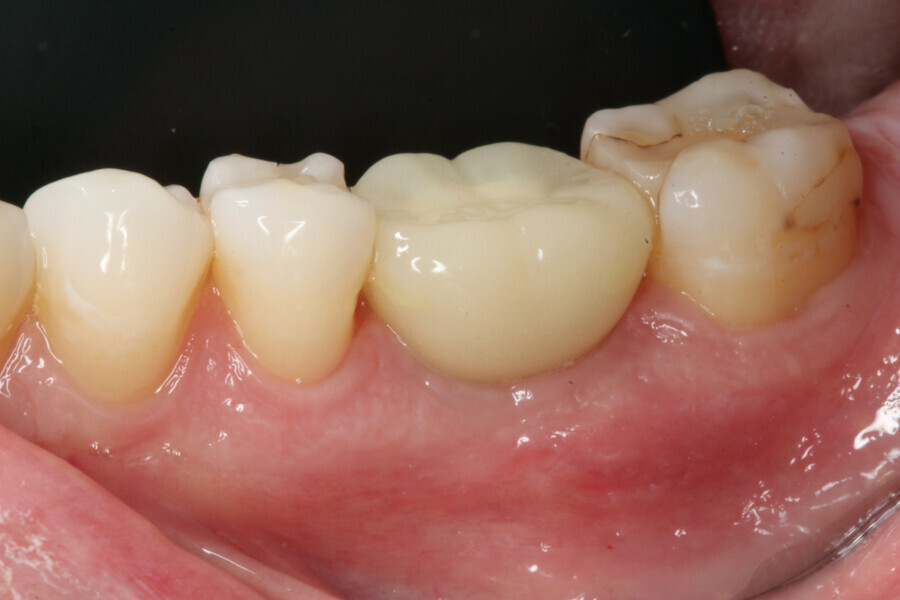

One week after implant surgery, healing was satisfactory and the abutment and provisional crown were inserted (Figs. 10–14).

During the healing period, the final crown was manufactured based on the Atlantis Core File. Eight weeks after implant placement, the soft tissue had healed well (Figs. 15 & 16) and was ready for the final zirconia crown (Fig. 17). Radiographic evaluation with the final restoration confirmed the successful outcome of the treatment (Fig. 18).